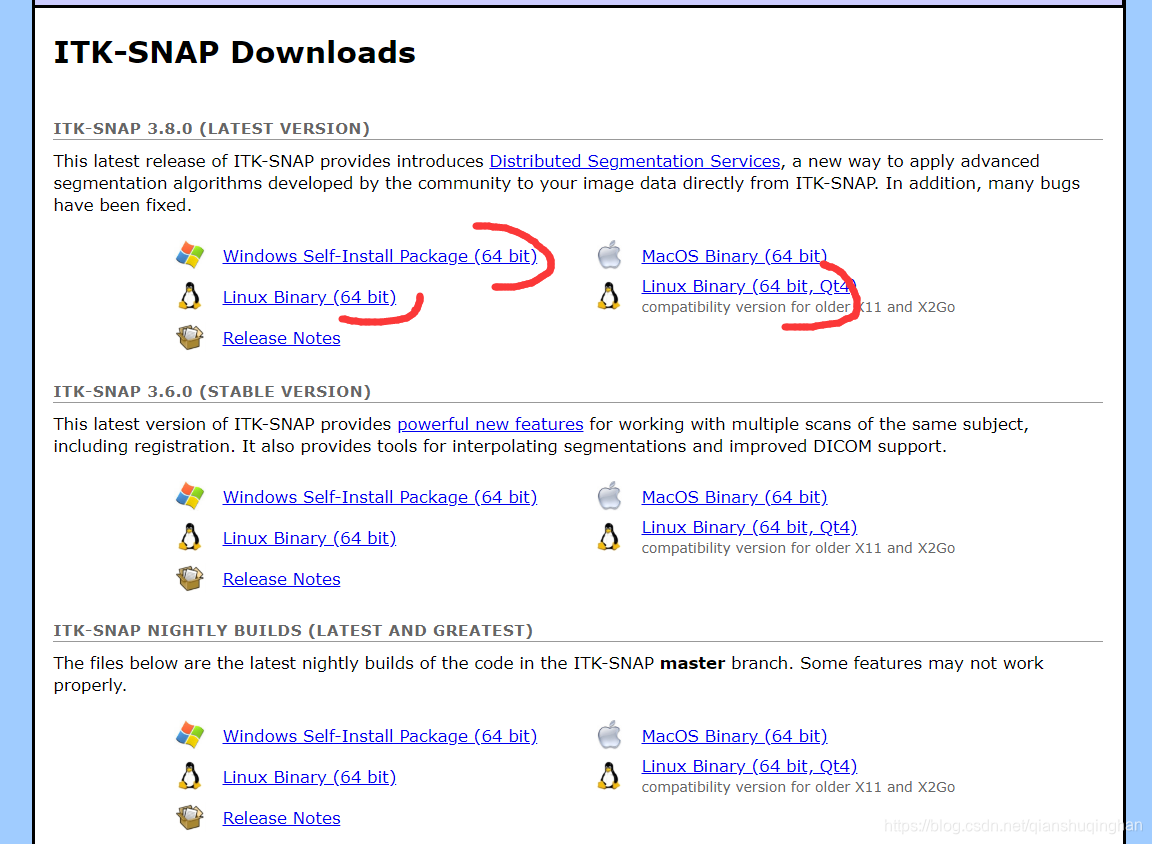

可从官网下载(建议最新版):http://www.itksnap.org/pmwiki/pmwiki.php?n=Downloads.SNAP3